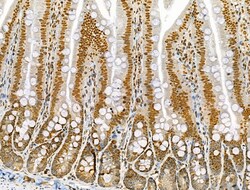

| Immunohistochemistry (Paraffin), Western Blot, Immunocytochemistry | |